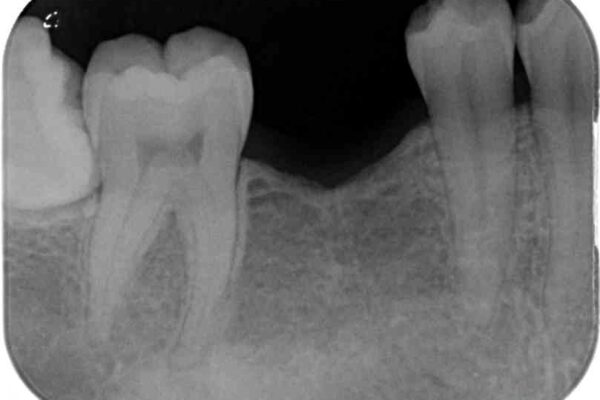

治療前

• 空いている時間を利用して通院 奥歯のインプラント治療 治療前画像